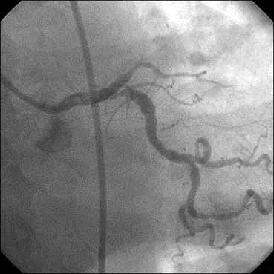

�Ǘ��72�Ώ����Brisk factor��HT, HL, DM�ł��B

��2�T�ԑO�̔��ǂƎv����Recent MI�ł��BLAD#7: total��Tristar3.0�~18?�����

�܂����B

����LCx ostium: 75%�ł��B������PCI���悤�Ǝv���̂ł����A�ǂ̂悤��strategy

���l������ł��傤���H

���Ȃ݂ɓ��@�ł�DCA�g�p�o���҂͂��܂���B

DCA�ł���l��A��Ă���A�Ƃ����I�������܂߂Č䏕��������K���ł��B

�X�������肢���܂��B

|

|

|

|

|

����������������������������������������������������������������������������